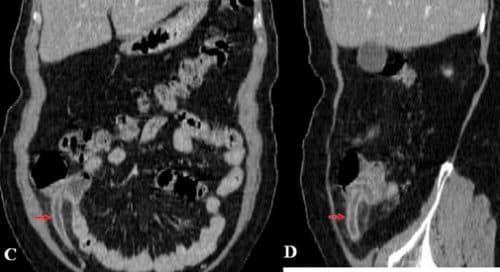

Ca 4: Bệnh nhân nữ 24 tuổi, đau hố chậu trái 2 ngày

Ruột thừa viêm mưng mủ nằm trong hố chậu trái.

Hình 4: A, gần gốc ruột thừa lòng chứa dịch nằm lệch hố chậu trái (mũi tên đỏ), manh tràng nằm ở đường giữa vùng chậu. B, thân ruột thừa to, ứ dịch, có sỏi phân trong lòng (mũi tên đỏ). C, ruột thừa sau sỏi phân lòng chứa đầy dịch to tròn (mũi tên đỏ). D, đầu tận cùng ruột thừa nằm ở hố chậu trái lòng chứa đầy dịch (mũi tên đỏ).

Kết luận: Manh tràng dài nằm ở lệch trái đường giữa vùng chậu, ruột thừa viêm mưng mủ nằm trong hố chậu trái.